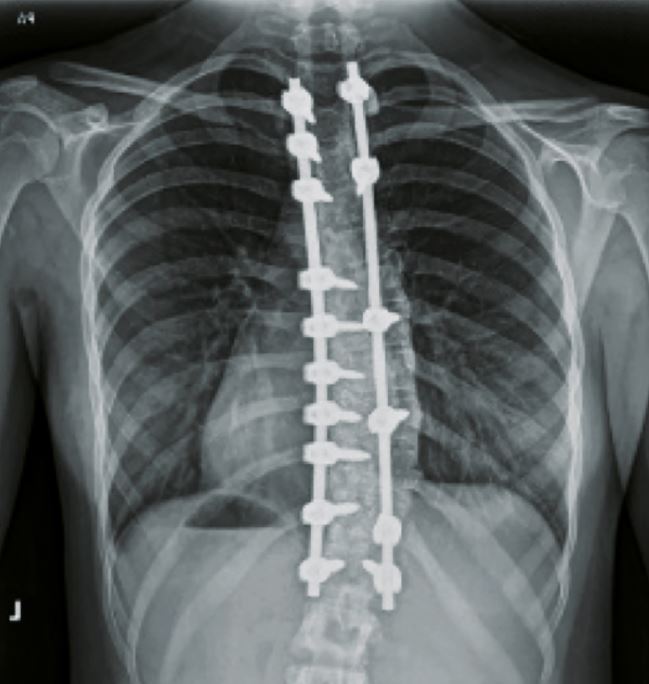

Abb. 3

Begradigung und Stabilisierung.